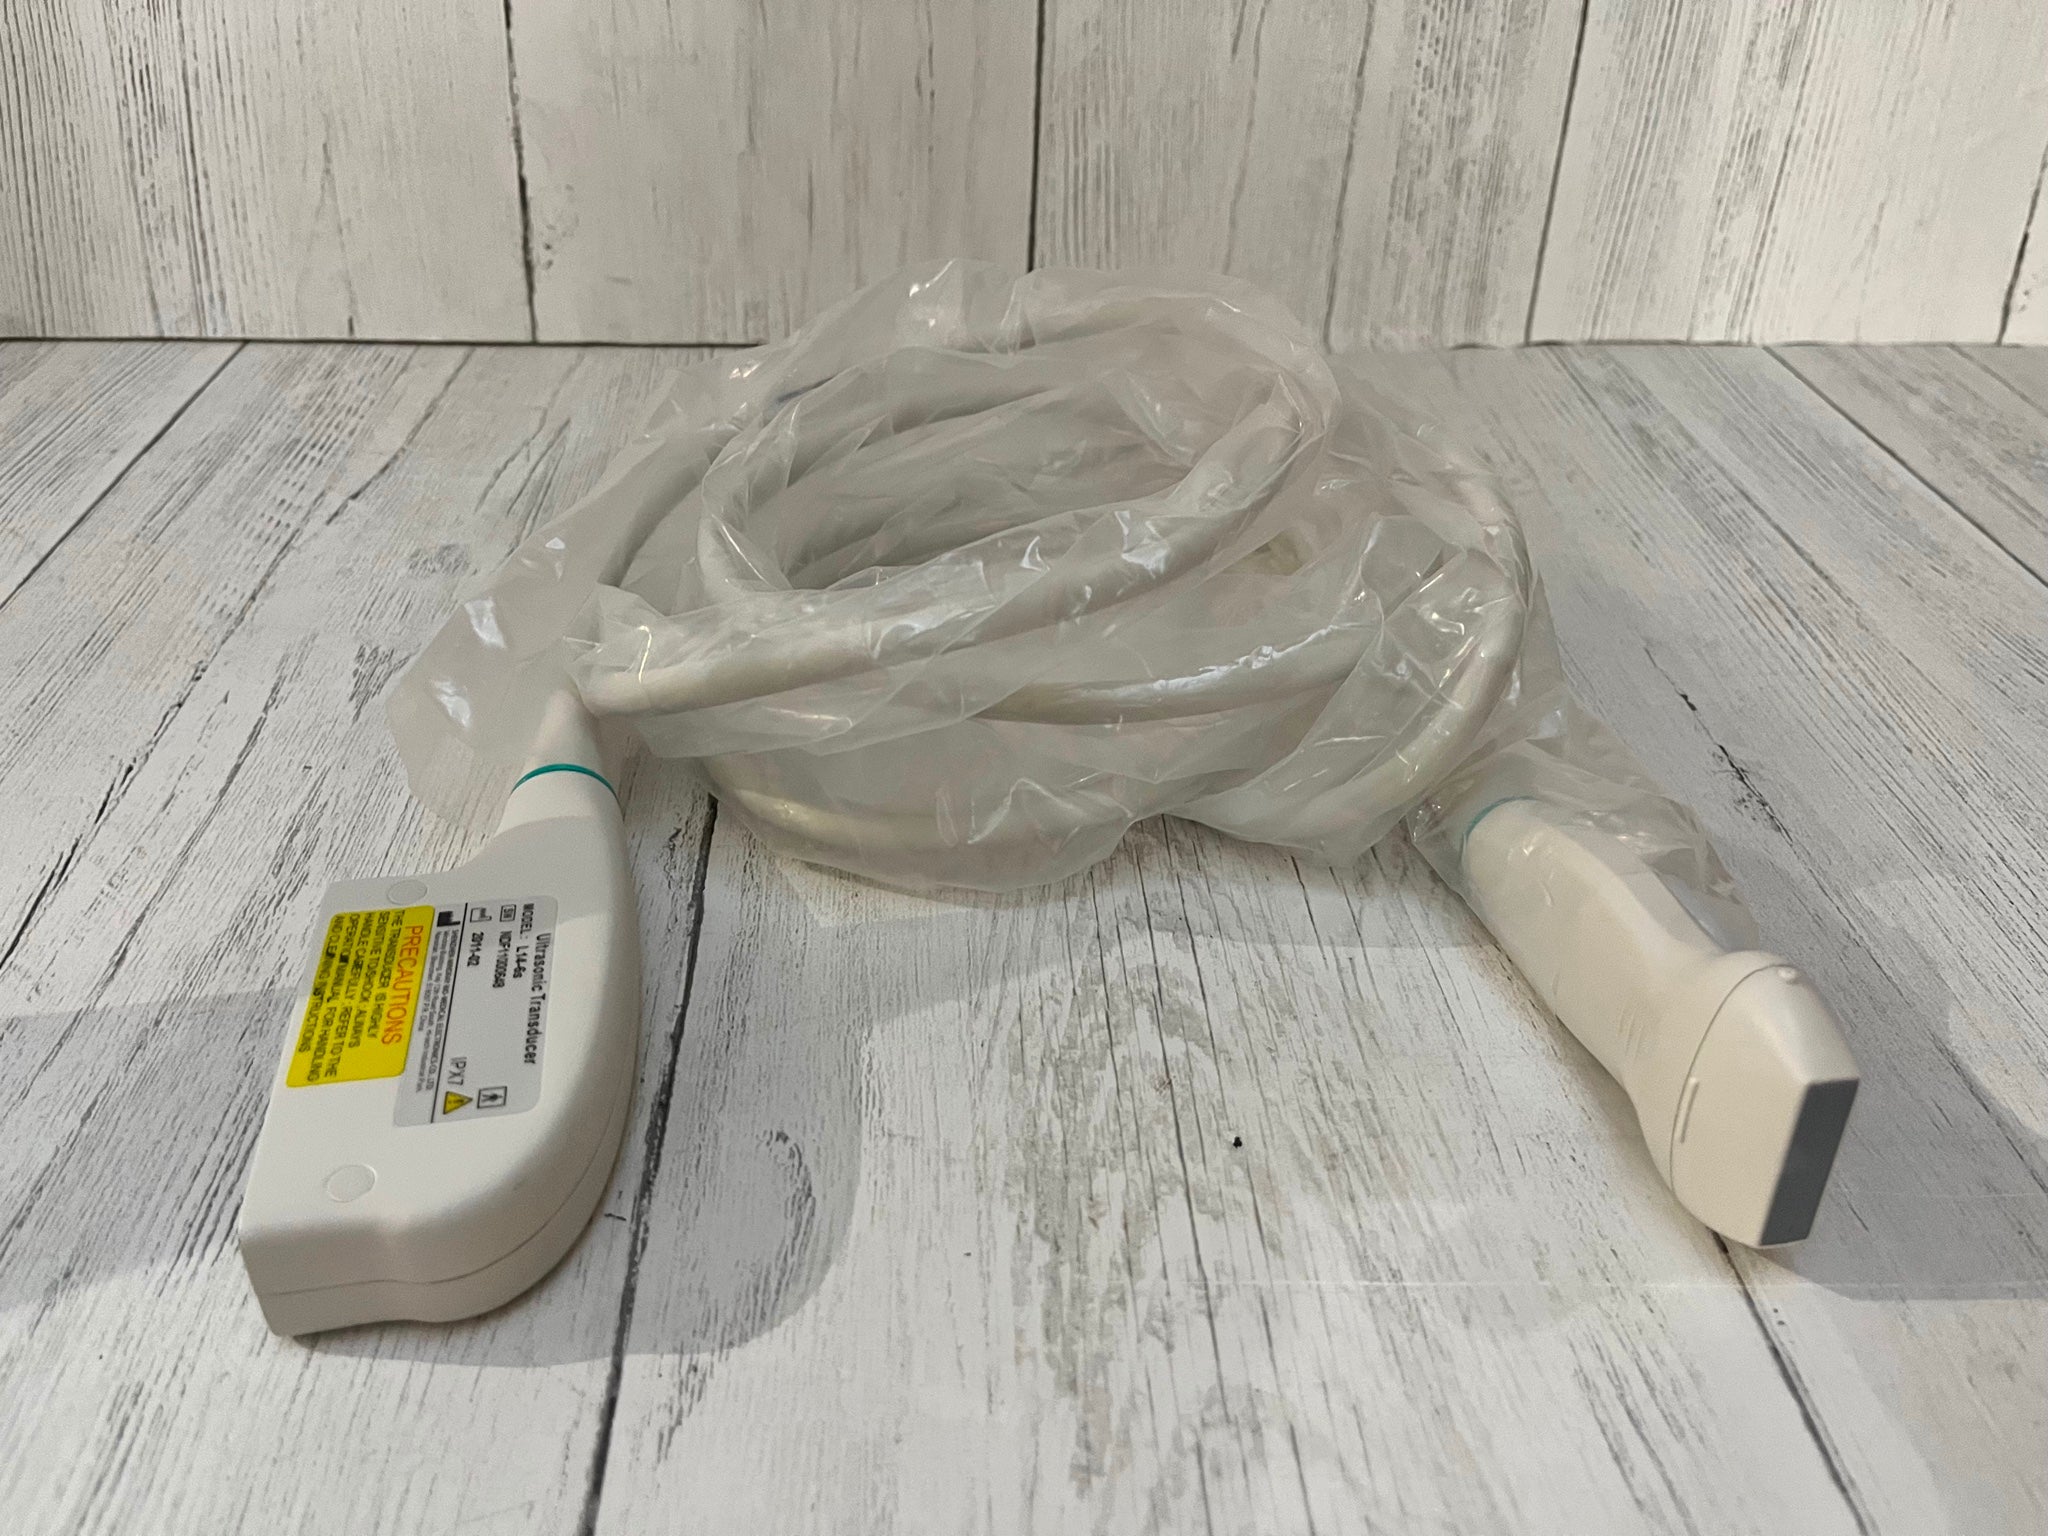

Philips C7-3 CONVEX PROBE FOR HD3 ULTRASOUND

Sale price$ 2,702.72